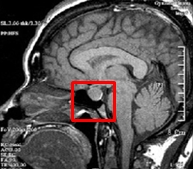

뇌하수체 기능부전(Hypopituitarism)

관련질환

뇌하수체의 악성 신생물

,

뇌하수체 양성 및 악성 신생물

뇌하수체 기능 항진

관련용어

난포자극호르몬